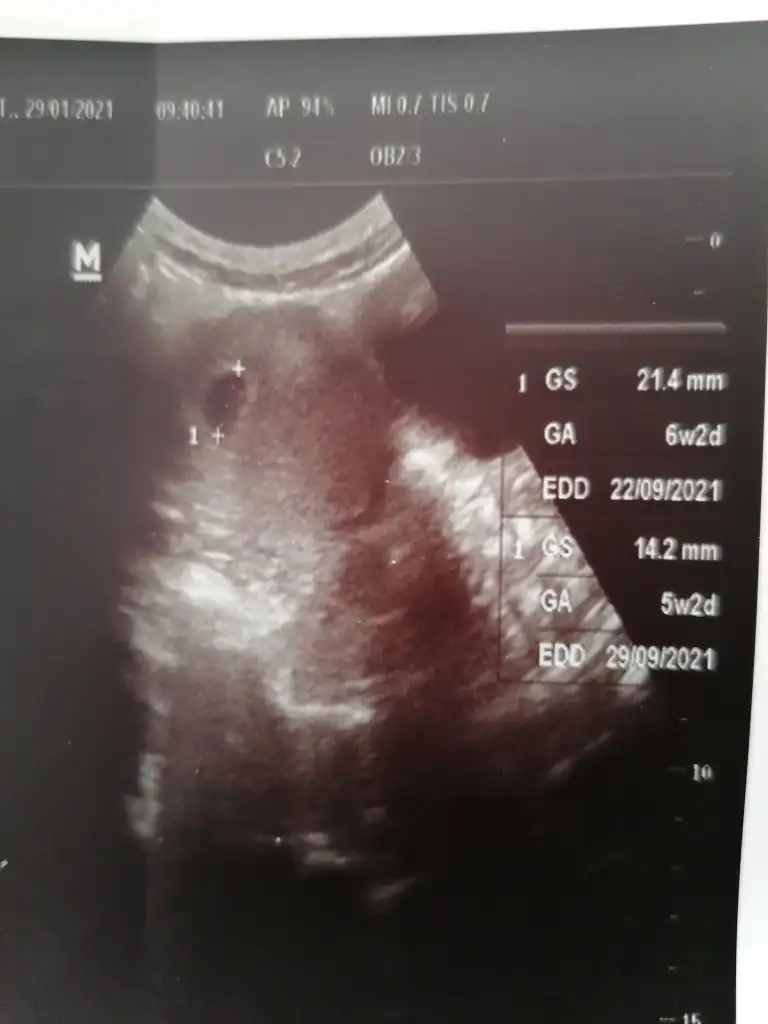

Kızlar merhaba ben 9. Haftadayım fikir vermesi için size yaşadığım süreçleri söylemek istedim. 5+0 da keseyi gördüm beta hcg değerim 5000 lerdeydi, 7+0 da bebek 6+4 görünüyordu kalp atışını duyduk, 8+1 de de bebek normal gelişim gününe gelmişti. Arada kahverengi akıntılarım oldu. Doktor normal olduğunu kanama alanı bulunmadığını söyledi. 12. Haftaya da kadar arada bu renkli akıntıların olabileceğini söyledi. Hepimiz için dua ediyorum Allah herkesin bebeğine sağlık versin inşallah. Hiç umutsuzluğa kapılmayın herkesin süreci farklı işleyebiliyor ama hayırlısı olsun hepimiz için